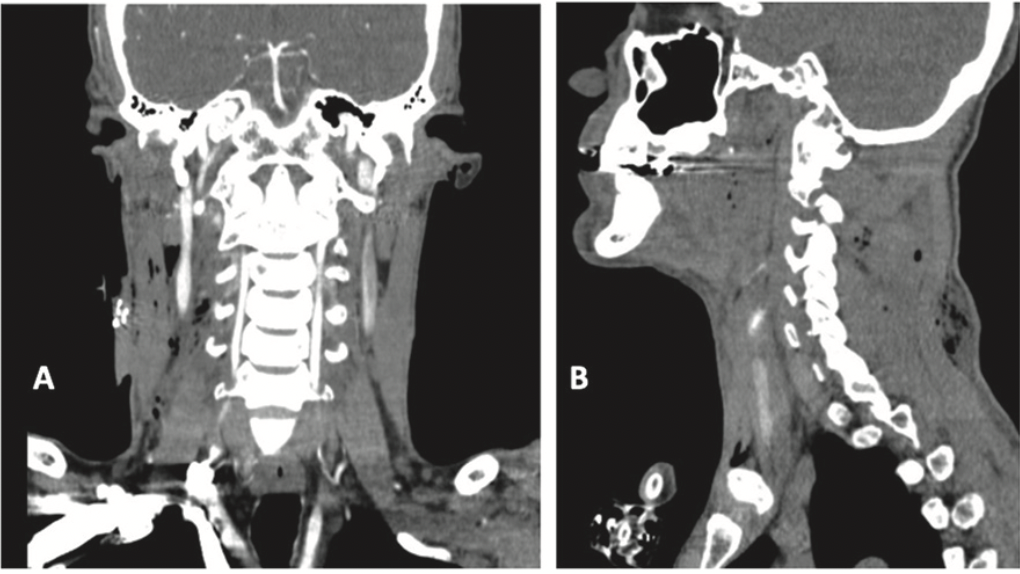

manuel antonio grez ibàñez, Rixio Abner Sánchez Medina